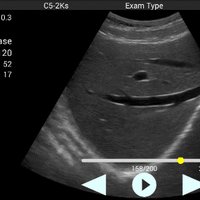

Konvexsonde (C5-2Ks) 3,3 MHz 2 - 5 MHz R50 Abdomen, Gynäkologie, Geburtshilfe, Urologie